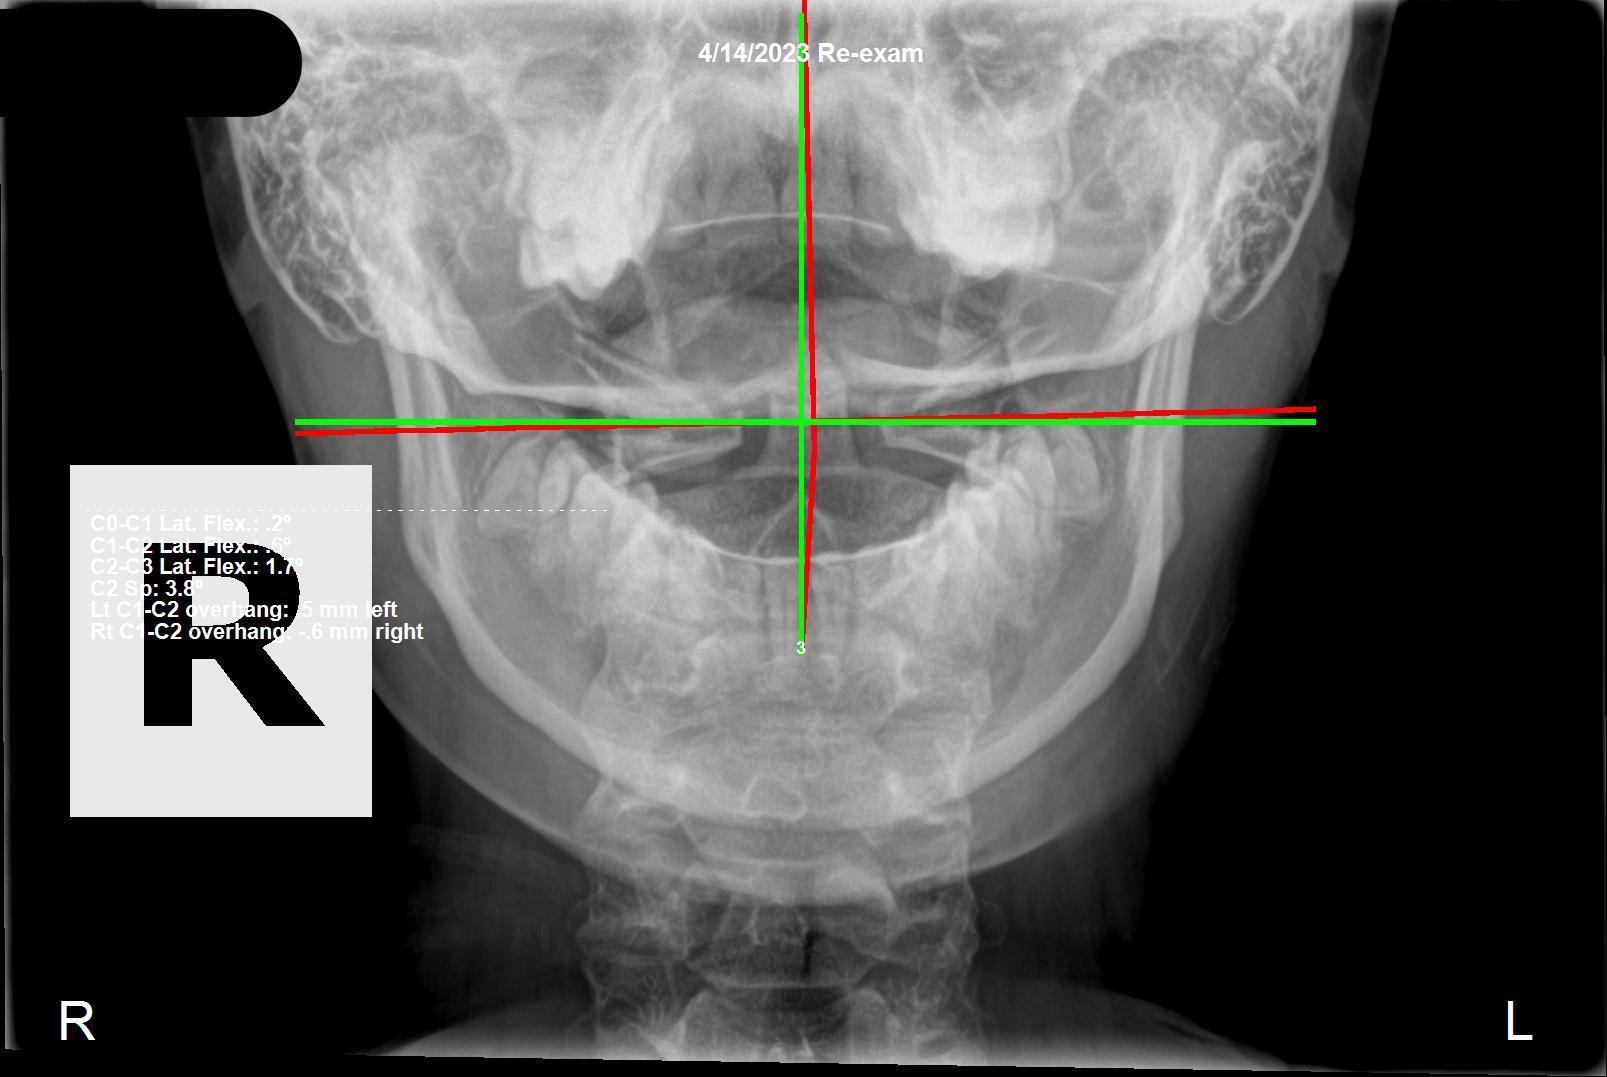

Correcting Neck Pain and Headaches